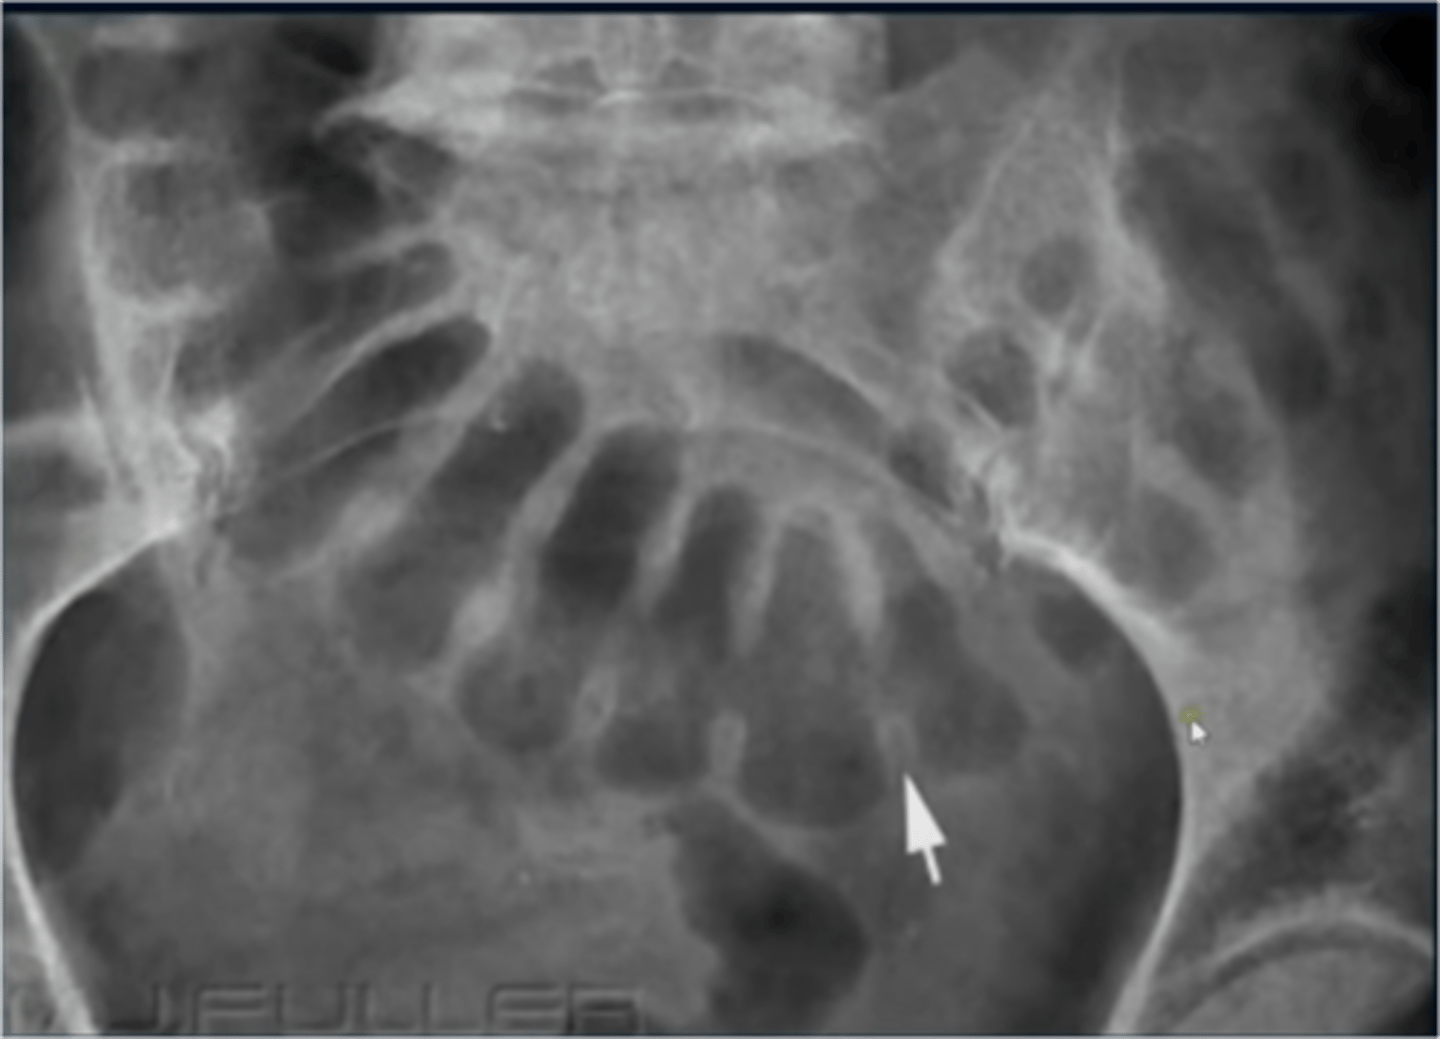

Toxic megacolon (shows location of large and small bowel)

Location of large bowel